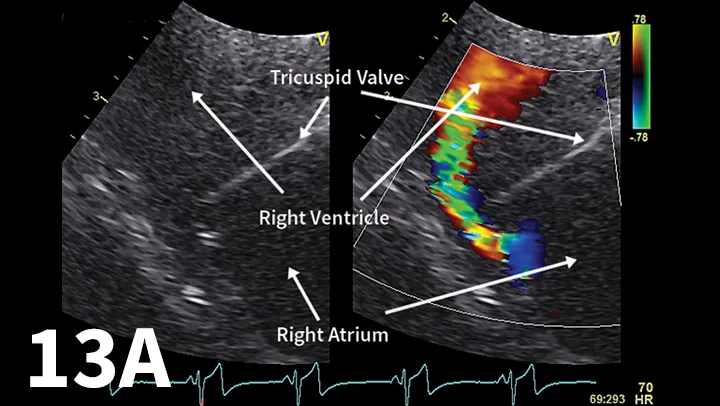

Figure 13A.

Left-sided apical view optimized for the right ventricle and right atrium showing the high-speed diastolic flow from the right atrium into the right ventricle (A). Right-sided view of the right atrium and right ventricle. The tricuspid value does not open completely. However, after ballooning the diastolic inflow from the right atrium to right ventricle, it is more laminar and not as turbulent as it was before ballooning (B).